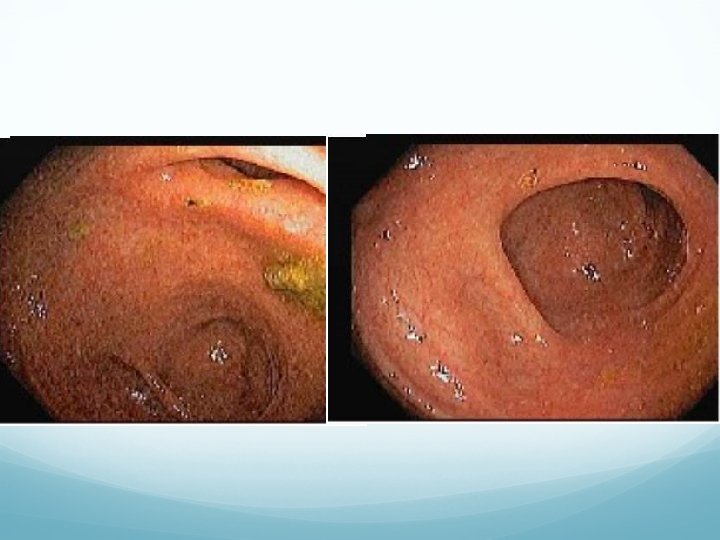

Colonoscopy

Colonoscopy Patulous ileo-cecal valve Normal terminal ileum Diffuse nodularity throughout entire colon, with mild erythema and loss of vascularity Random biopsies in right colon, left colon, and rectum were taken and submitted separately